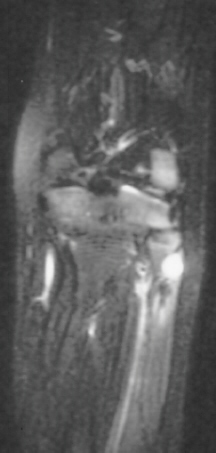

Radiographic examination of the left knee revealed no osseous abnormalities . A fullness of the soft tissues was evident over the fibular head. MRI examination of the left knee displayed a 2 cm. by 0.8 cm. lobulated mass in the region of the common peroneal nerve with no enhancement . On the T-2 weighted sequences there was abnormal increased signal of the tibialis anterior, extensor digitorum longus and peroneus longus muscle bellies suggesting atrophy . EMG/NCS were performed which clearly documented electrodiagnostic evidence of a severe peroneal neuropathy distal to the take-off of the nerve to the short head of the biceps.

Ganglion cysts causing compressive peripheral neuropathies are an unusual, but when combined not an uncommon etiology. Ganglia are especially common in the region of the hand and wrist although they usually do not result in a compressive neuropathy. Several reports have been published documenting nerve compression in the upper extremity in the following locations: ulnar nerve in Guyon's canal, motor branch and cutaneous branch of the median nerve by a volar ganglion, and posterior interosseous nerve at the proximal radio-ulnar joint.

Peripheral nerve compression secondary to ganglion cysts in sites other than the upper extremity have been reported with increasing frequency probably because of improved imaging modalities. These locations include the tarsal tunnel and the posterior tibial nerve, the spino-glenoid notch and the suprascapular nerve and spinal nerve roots compressed by ganglion cysts arising from the facet joints.